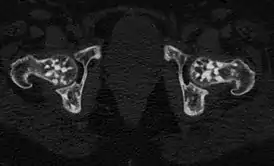

![]() Проявления остеопойкилии в костях таза и головках бедренных костей (компьютерная томограмма). | |

Заболевание является системным, проявляется очагами остеосклероза округлой и овальной формы, как правило приблизительно одинакового калибра, от 2 мм до 20 мм. Очаги могут располагаться практически во всех костях, однако наиболее часто выявляются в коротких костях запястья и предплюсны, метафизах и эпифизах длинных трубчатых костей (плечевых, бедренных) при интактности их диафизов.[6]